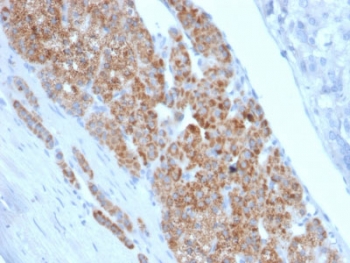

StAR Antibody Protein Microarray Validated Clone STAR/2140. Immunohistochemistry analysis of Steroidogenic Acute Regulatory Protein (StAR / STARD1) in FFPE human testicular carcinoma tissue using a mouse monoclonal antibody validated by protein microarray specificity screening. HRP-DAB brown cytoplasmic staining highlights tumor cells with steroidogenic differentiation, consistent with the mitochondrial localization of StAR in steroid hormone-producing cells, while surrounding stromal and non-steroidogenic tissues show minimal staining. Heat-induced epitope retrieval was performed by boiling tissue sections in 10 mM citrate buffer, pH 6, for 10-20 minutes followed by cooling at room temperature for 20 minutes prior to staining.